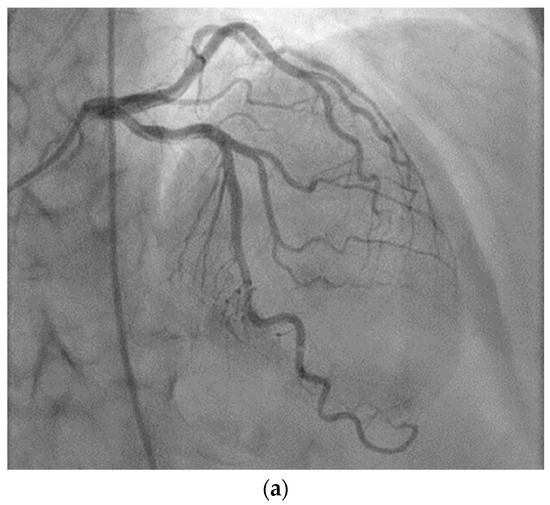

2. Case Presentation